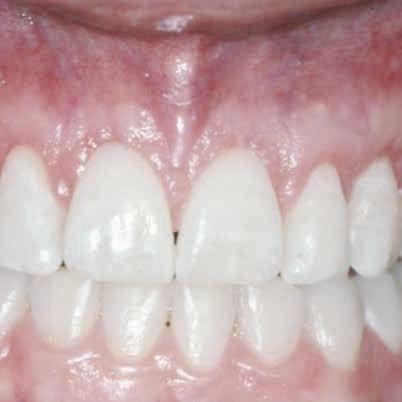

An evolution in patient demands has reached an unprecedented level of exactness. Patients are even more demanding when it comes to restoring nonesthetic areas than esthetic areas. This increase in esthetic demand does not go unjustified. There is a relationship between a person’s physical appearance and their self-esteem. Researchers have found that a person’s face is the primary source of determining physical attractiveness.1,2

Increased gingival exposure on smiling, termed excessive gingival display (EGD) has been an ongoing point of concern for both the patient and clinician. Patients will often refer to this as a “gummy smile.” The clinician must fully understand the multifactorial nature of this situation to provide patients with a satisfactory solution. A thorough examination, an accurate diagnosis, and proper planning are imperative for achieving predictable and esthetically superior results.

Several conditions are known to cause EGD, including vertical maxillary excess, hypermobile or short upper lip, dentoalveolar extrusion, gingival overgrowth, and altered passive eruption (APE).3 Management depends primarily on the underlying cause. If EGD is due to vertical maxillary excess, orthognathic surgery is often indicated to correct the skeletal anomaly. Hypermobile or short upper lip can be corrected by means of lip repositioning surgery or temporarily by means of botulinum toxin injections. Another etiologic factor is dentoalveolar extrusion, which is usually corrected with orthodontic intrusion. Furthermore, in cases of gingival overgrowth, external bevel gingivectomy is often sufficient. Finally, EGD might be due to APE, which requires an esthetic crown lengthening procedure. Because combined etiologies more commonly underlie EGD, multitreatment interdisciplinary approaches are frequently indicated.3

Despite major esthetic advances in periodontal therapy, the preservation of a sound periodontium remains a prerequisite of a successful esthetic and functional restoration. Thorough knowledge of anatomy and the interplay between a restoration and the periodontium is essential for achieving a successful and predictable esthetic outcome. Communication between the prosthodontist and periodontist is a crucial factor in the treatment of such cases.

CONCLUSIONS

A surgical guide used to perform esthetic crown lengthening is a time-efficient tool that facilitates predictability and reproducibility. After assessing the location of the alveolar bone and the CEJ, several techniques can be used to guide the surgical procedure. These include bleeding points, Chu proportion gauge, and laboratory-fabricated surgical guides. When restorative treatment is indicated, esthetic crown lengthening can, alternatively, be guided by existing teeth preparation finish lines. The use of digital technologies simplifies fabricating surgical guides and minimizes clinical time.